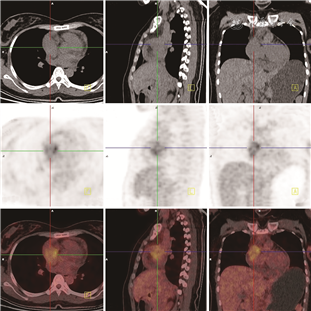

患者女,26岁,主因“间断胸痛、胸闷、呼吸困难40余天”于2019年10月22日入院。患者40余天前出现间断胸痛、胸闷、呼吸困难症状,伴乏力、口唇紫绀、恶心呕吐,呕吐物为胃内容物,后出现右上腹疼痛伴右侧肩部疼痛。否认高血压及其他心脏病史,无家族遗传病史。入院体格检查:血压95/52 mmHg(1 mmHg=0.133 kPa),心率108次/min,律齐,肝颈静脉回流征阴性,双肺呼吸音低,各瓣膜区未闻及杂音。PET-CT(图1):右心房区见放射性浓聚灶,最大标准摄取值(SUVmax)约7.1,大小约4.1 cm×2.2 cm,心包见液性密度影,其余各系统未见浓聚灶。超声心动图:右心房近上腔静脉侧可探及范围约3.9 cm×1.9 cm低回声光团附着,形态规则,边界欠清,心包腔内可探及中量液性暗区。术前经食道超声心动图再次确认为右心房占位性病变(图2)。